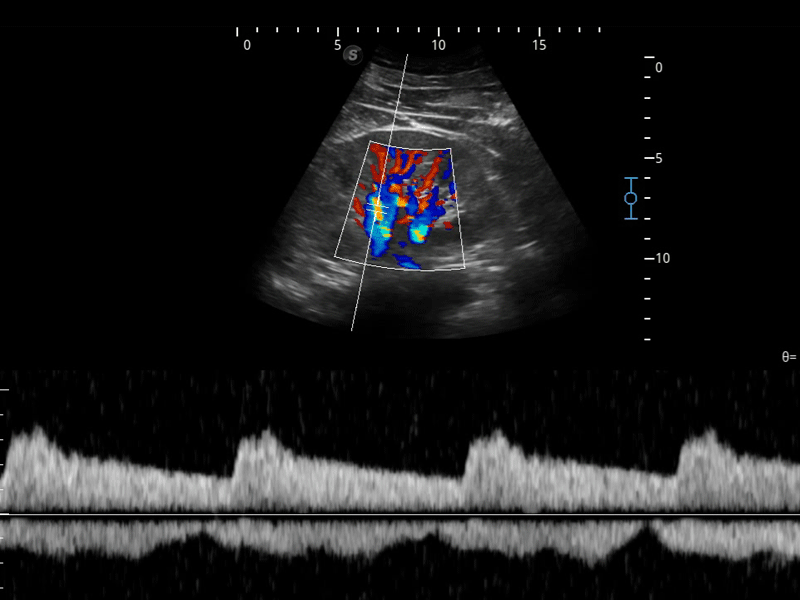

SR Flow高分辨率血流成像

高分辨率血流成像技术提高了对低速血流信号的检测能力。在提高空间分辨率的同时,也克服了血流外溢现象,为用户提供更加真实的血流动力学信息。